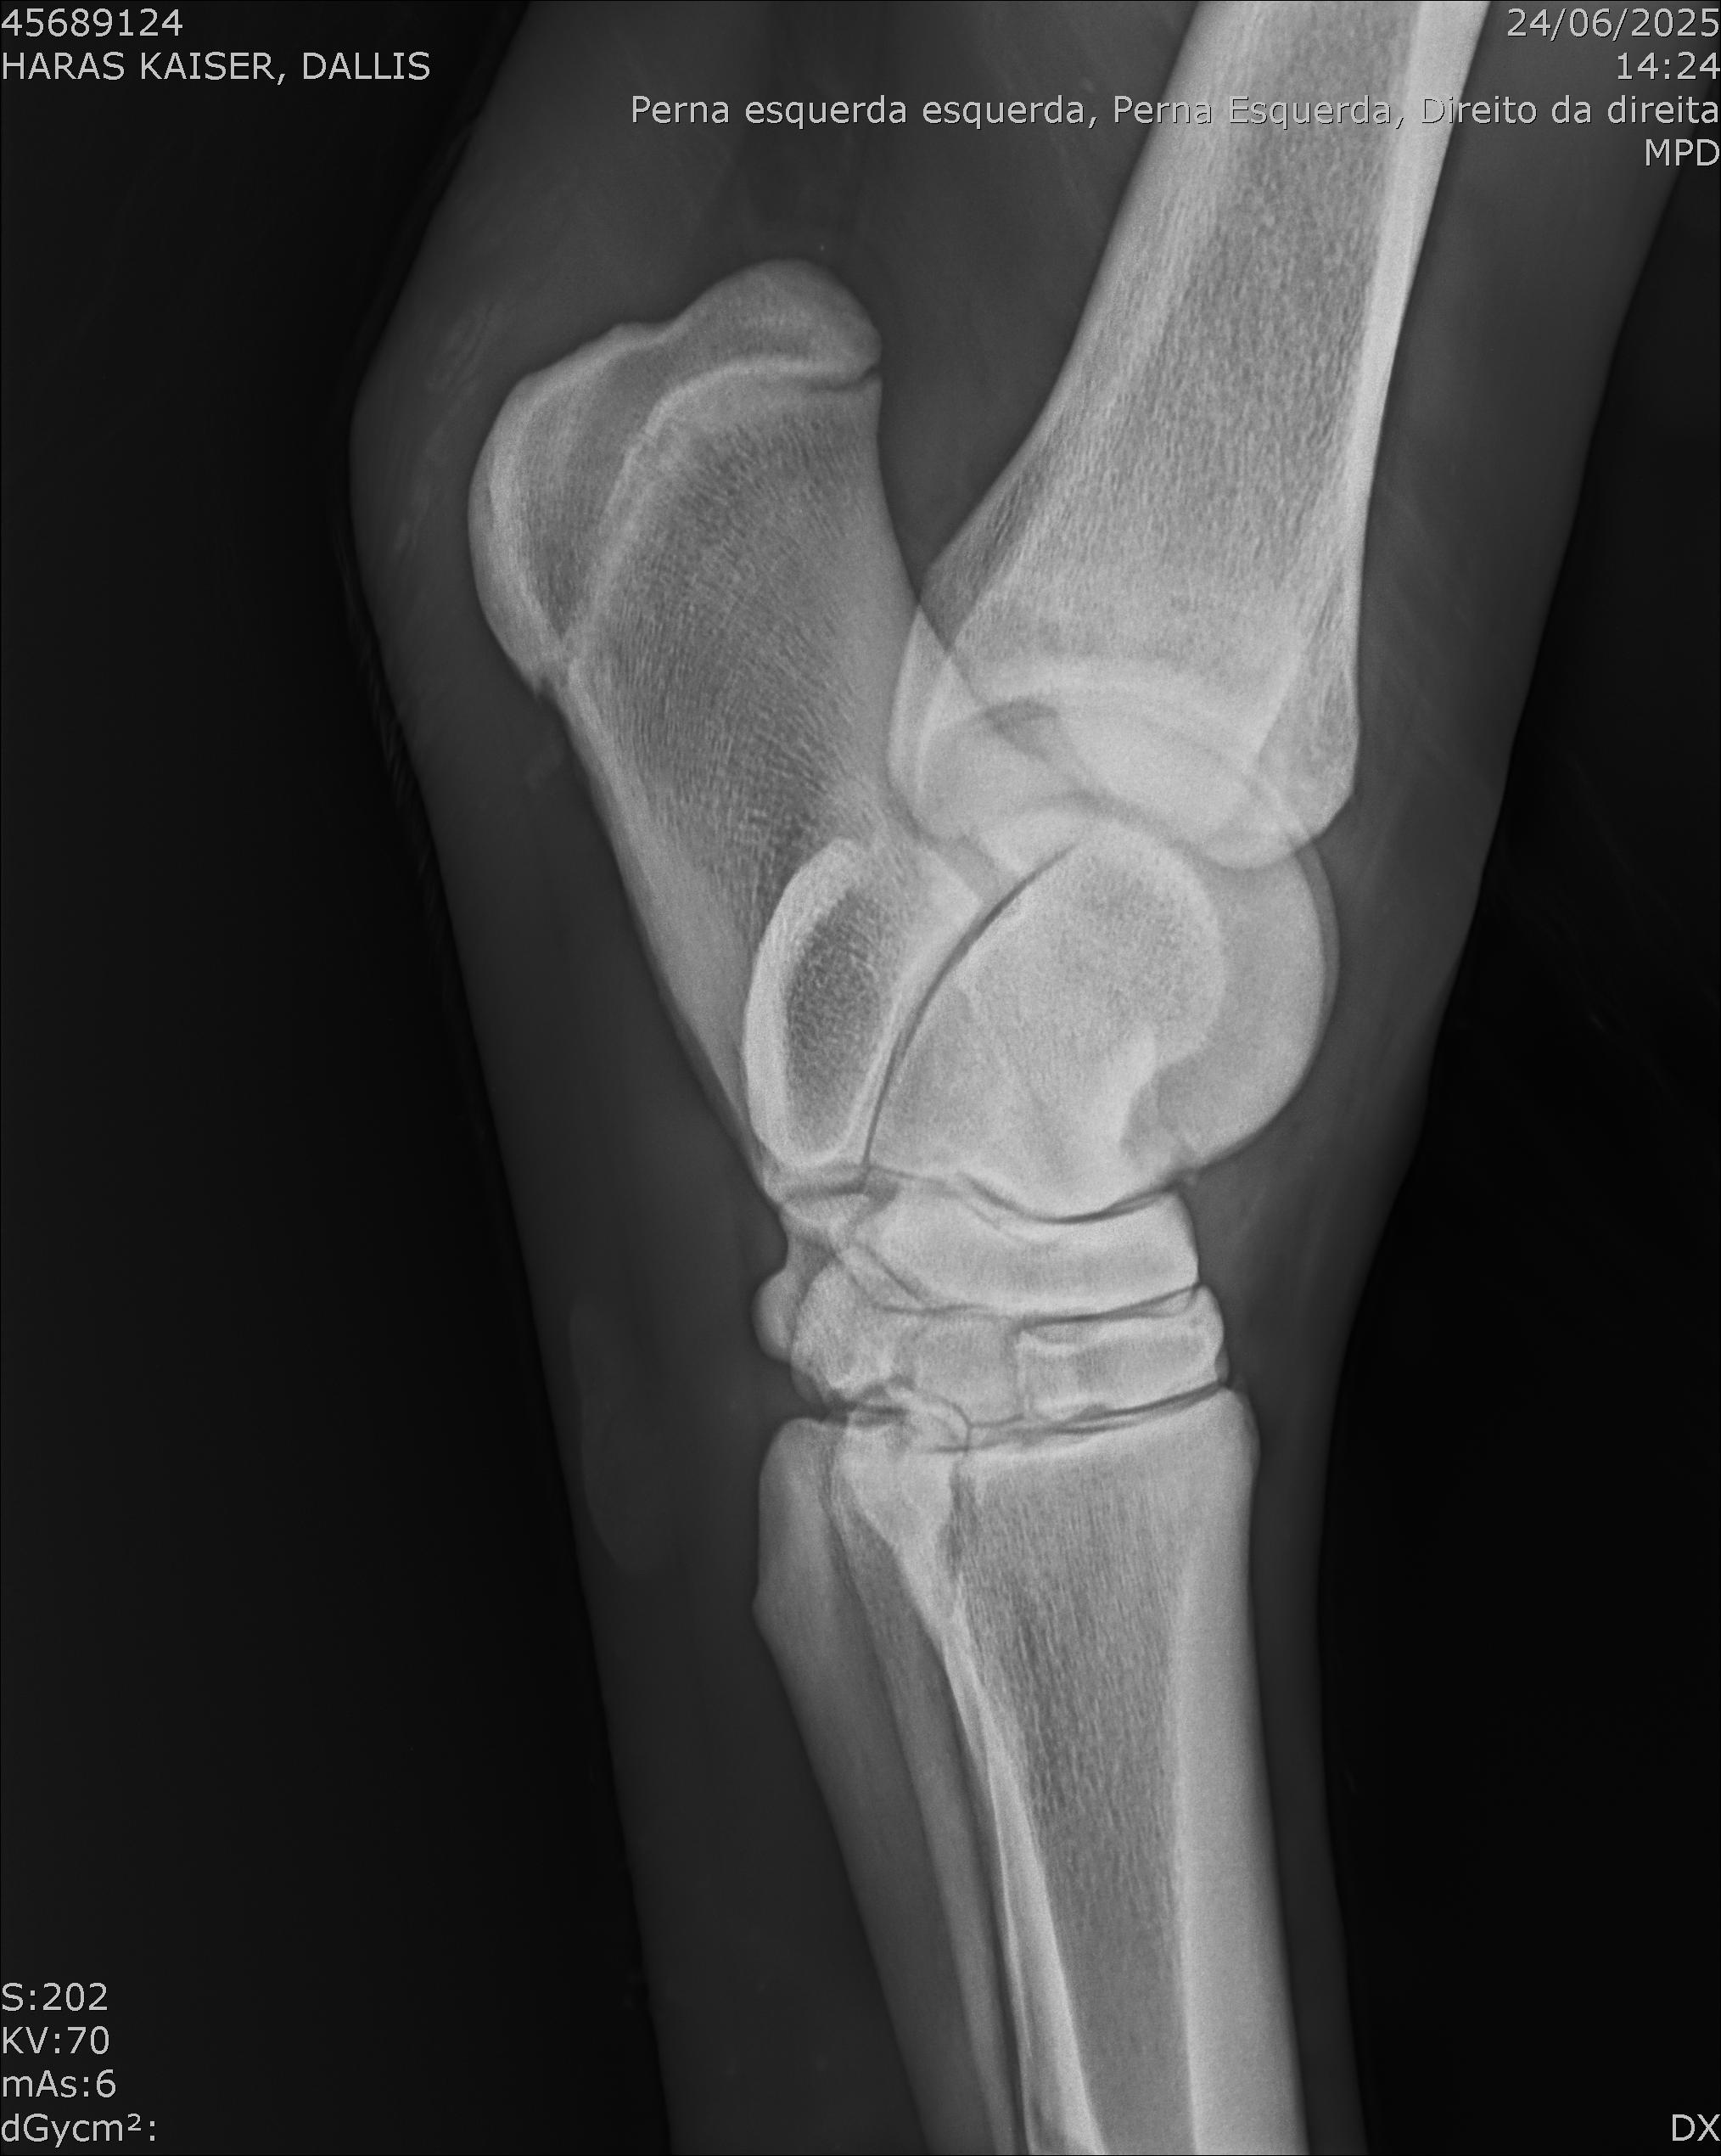

:: RAIOS-X DO LOTE